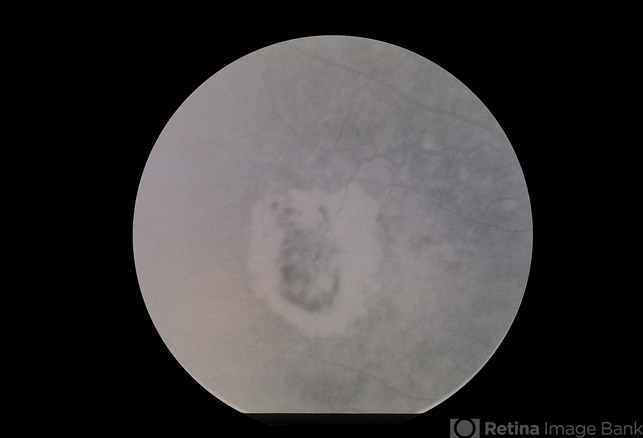

- ARMD SRNVM

- Condition/keywords

- subretinal neovascularization (SRNV)

- ARMD, SRNVM, 79-year-old white female, 20/300.